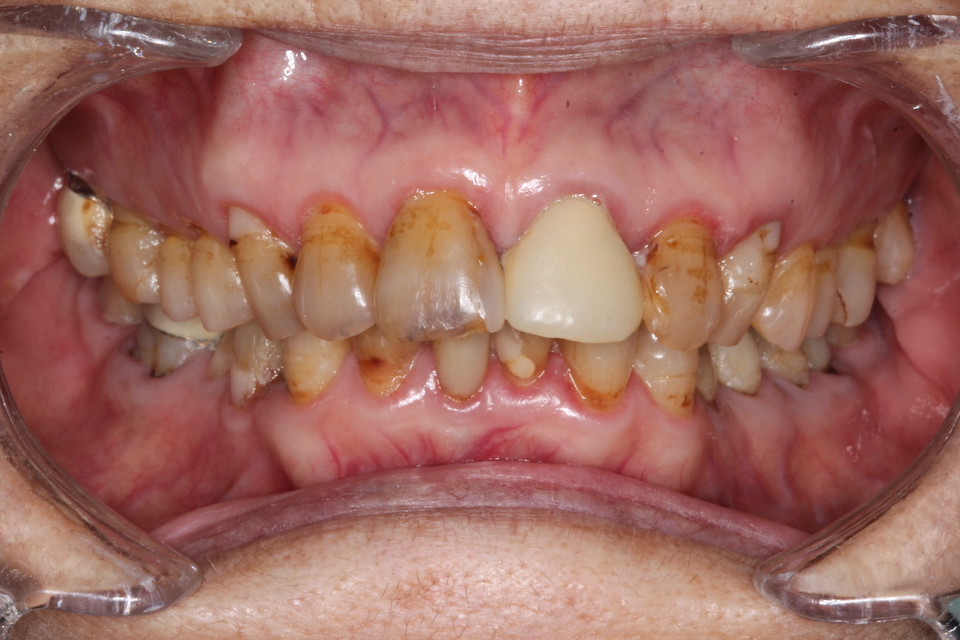

今日90歳

3年毎の画像を遡って見てみましょう。